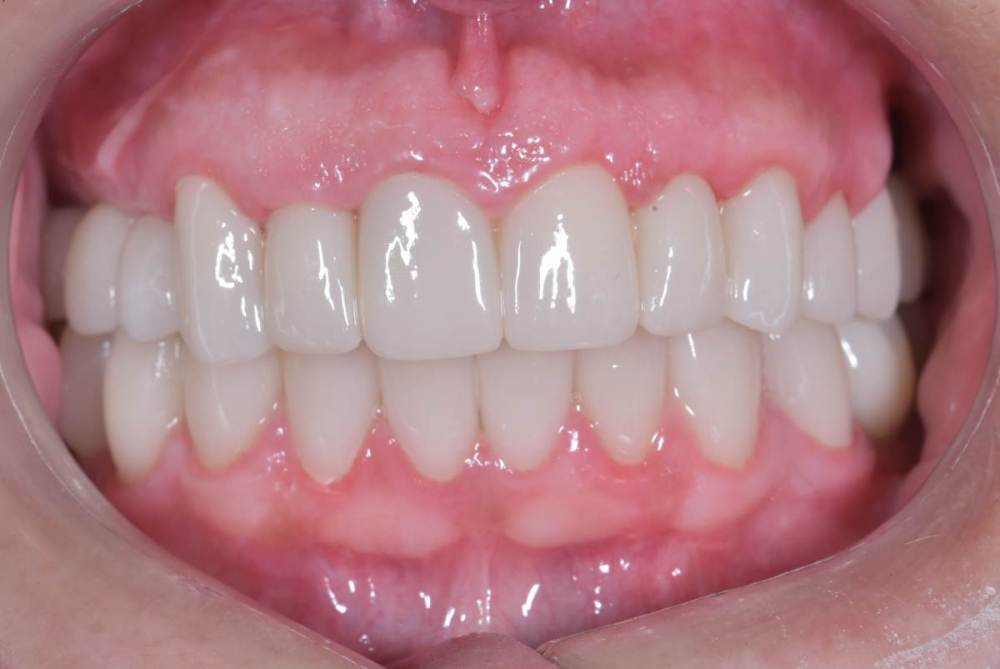

TIGER Опубликовано 3 ноября, 2023 Поделиться Опубликовано 3 ноября, 2023 Периохирургия способна на чудеса)не спешите удалять зубы 5 1 Ссылка на комментарий

TIGER Опубликовано 3 ноября, 2023 Автор Поделиться Опубликовано 3 ноября, 2023 @АнтонТЛТ Антон честно,лень было)Пациентка довольна как слон,эстетические требования приемлимые.Поэтому не стал навязывать доп манипуляцию.Поэтому тут считаю результат приемлимый Ссылка на комментарий